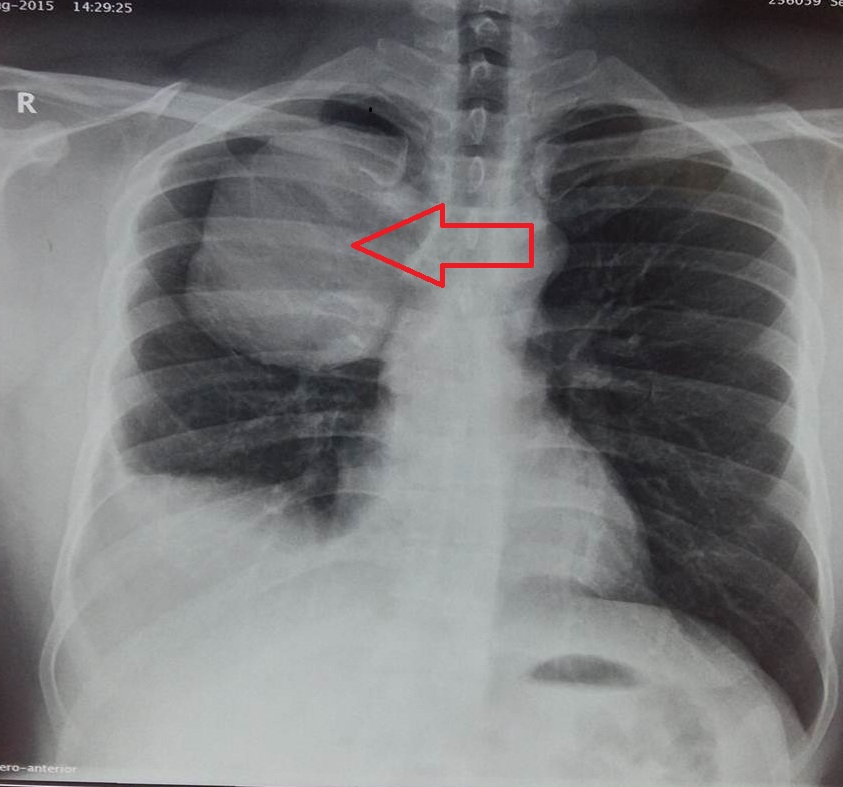

- Figure 1 - Right sided pleural effusion

- Figure 2 - Right sided hemothorax